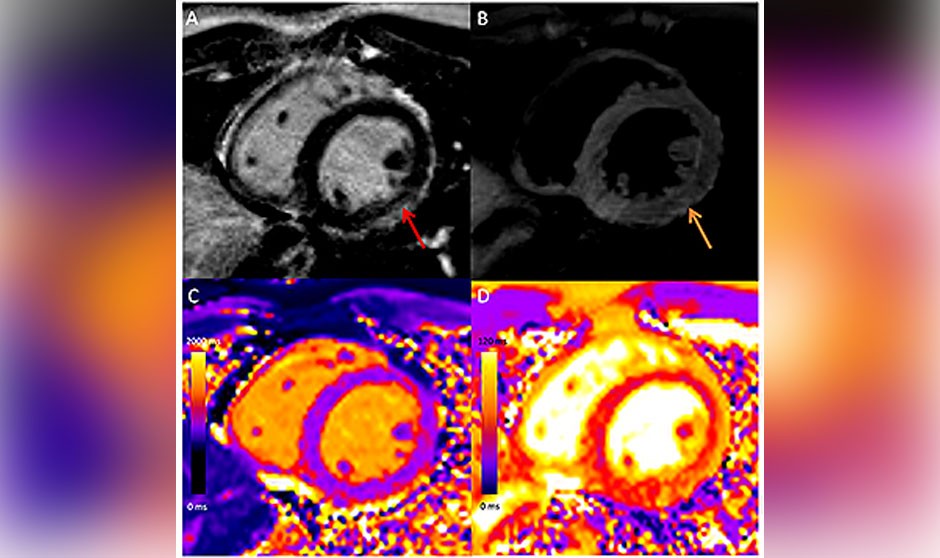

En el estudio, revisado por pares y publicado en la revista Radiology, los investigadores aseguran que la resonancia magnética cardíaca ha mostrado un “patrón similar” de la lesión miocárdica en la miocarditis asociada a la vacuna en comparación con otras causas, aunque las anomalías “fueron menos graves, con afectación septal menos frecuente y sin eventos adversos durante el seguimiento a corto plazo”.

En cuanto a los hallazgos de la resonancia magnética en la miocarditis asociada a la vacuna mostraron un realce tardío de gadolinio en el 81 por ciento de los casos y una disfunción ventricular izquierda en el 29 por ciento.

“La resonancia magnética cardíaca mostró que en comparación con otras causas de miocarditis los pacientes con miocarditis asociada a la vacuna tenían menos deterioro funcional y anomalías miocárdicas menos extensas. Mientras que los pacientes con miocarditis tras superar el covid y otras miocarditis tenían una mayor prevalencia de anomalías que involucraban el tabique interventricular y peor lesión miocárdica medida por mapeo T1”, concluyen los investigadores.